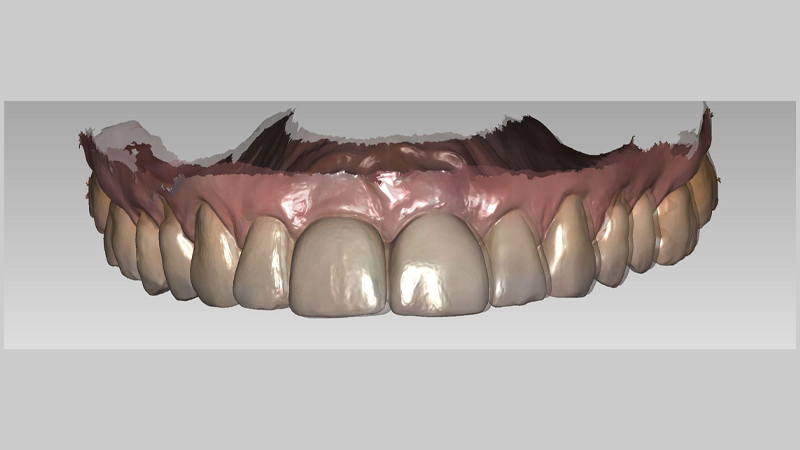

At Chrysalis Dental Centres, we employ the DEXIS IS 3800WⓇ (DEXIS, Hatfield, PA, USA) in combination with exocadⓇ software (exocad GmbH, Darmstadt, Germany) to perform these overlays (Figure 3). This scanner offers high resolution and wireless flexibility, but the principle of the method is what matters: any modern IOS capable of accurate surface capture, paired with alignment software, can reproduce this workflow with similar effectiveness.12

Fig. 3